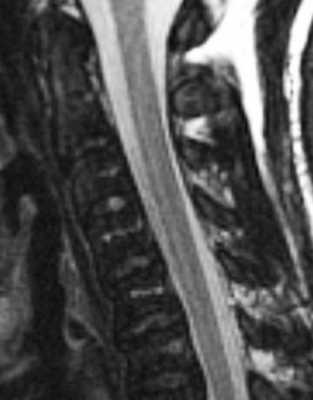

(Слева) Сагиттальный срез, Т2-ВИ: диффузное утолщение и гиперинтенсивность сигнала шейного отдела спинного мозга у пациента, получавшего ранее лучевую терапию по поводу рака носоглотки.

(Справа) Нa сагиттальном Т1 -ВИ с КУ у этого же па -циента определяется пятнистое контрастное усиление на протяжении нескольких сегментов в пределах утолщенного участка спинного мозга. Обратите также внимание на патологические снижение интенсивности сигнала паренхимы спинного мозга выше и ниже очагов усиления вследствие отека спинного мозга.

(Слева) Сагиттальный срез, Т1-ВИ: случай распространенных постлучевых изменений спинного мозга в виде значительного и диффузного веретеновидного утолщения нижнешейного и грудного отделов спинного мозга. Область облучения ограничена жировыми изменения костного мозга — тела С6, С7 и верхнегрудных позвонков.

(Справа) Нa сагиттальном Т2-ВИ пациента, получавшего лучевую терапию по поводу меланомы, определяются признаки распространенной постлучевой миелопатии шейного и грудного отдела спинного мозга в виде диффузной гиперинтенсивности сигнала этих сегментов спинного мозга.